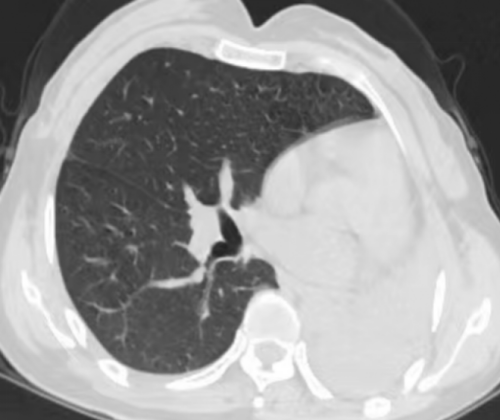

呼吸与危重症医学科就医,胸部CT检查显示左肺未显影,左肺“消失”不见了?

吴丽胸部CT显示左肺“消失”

“为了找回‘消失’的肺,我们给她安排了胸部增强CT。发现其左主支气管狭窄、远端及各叶段支气管闭塞并左肺团片影及肺不张。”据立博体育|实时赛事直播与比分|权威专家分析与体育竞猜平台

呼吸与危重症医学科内镜诊疗部副主任医师刘超群介绍。为进一步明确病因,完善支气管镜检查,检查见左主支气管瘢痕闭塞,未见远端管腔。据了解,吴女士三年前被确诊为支气管结核、支气管狭窄,医生开了抗结核药物治疗,并叮嘱她要定期复查。但症状明显好转后,吴丽就放松警惕,没有规律治疗了。结合患者既往病史,诊断为支气管结核(管腔闭塞型)、左肺完全不张。